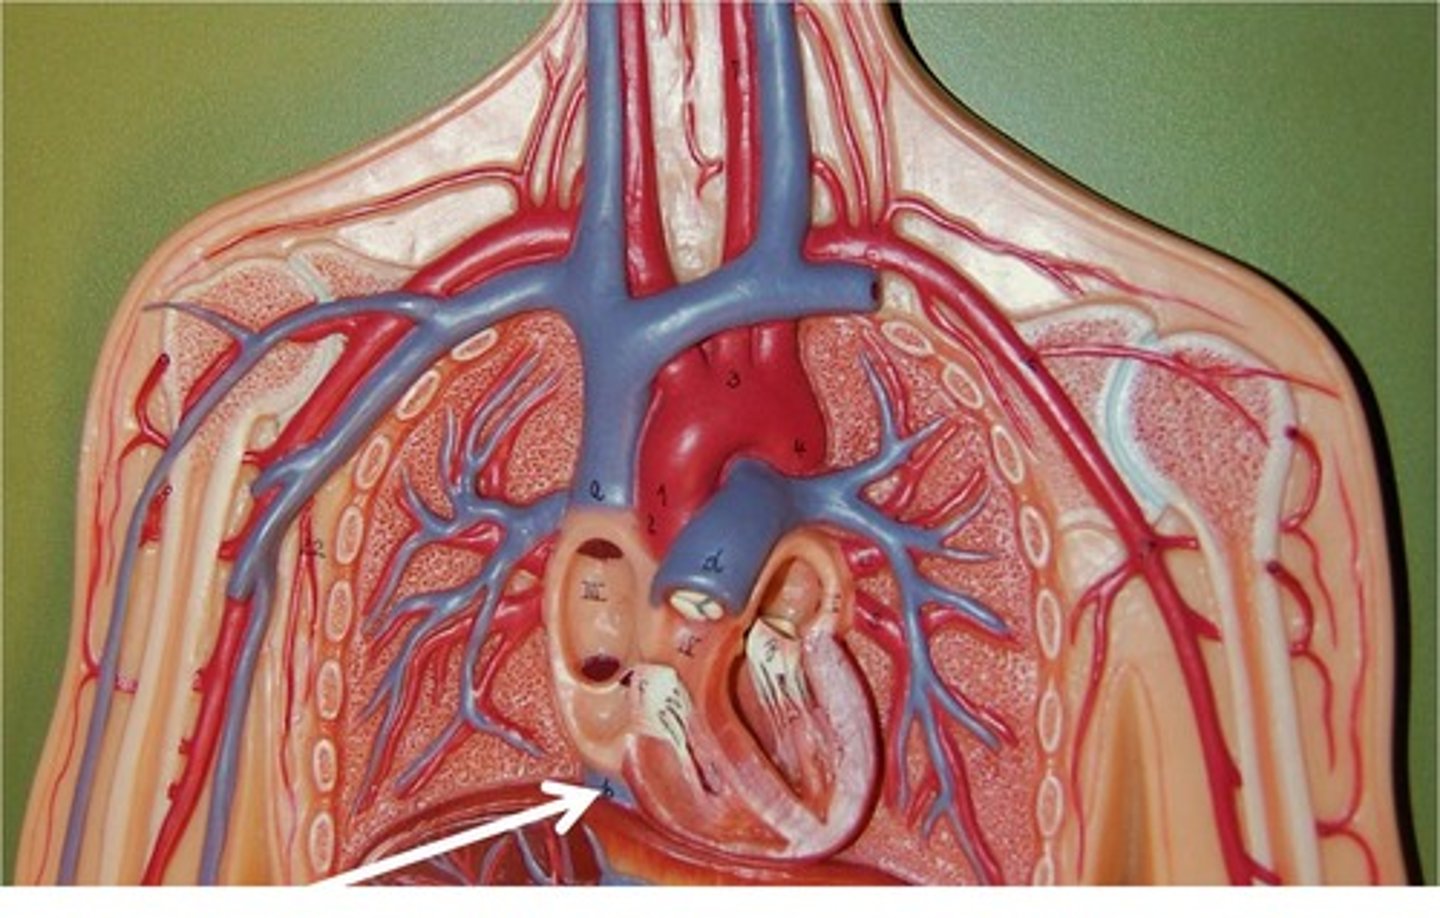

ascending aorta

branches include right and left coronary arteries

right coronary artery

left coronary artery

brachiocephalic artery

feeds right common carotid artery and right subclavian artery

aortic arch

feeds brachiocephalic artery, right and left common carotid arteries, right and left subclavian arteries

superior vena cava